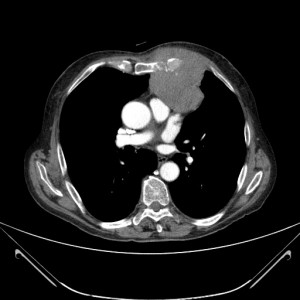

En este caso, la rx de tórax muestra una lesión compatible con una masa de la misma densidad que el corazón, y esta sospecha se ve reforzada por la presencia de una tumoración torácica palpable. Por lo que la prueba indicada sería el TAC de tórax para conocer la extensión, morfología así como la localización exacta de la masa.

La TAC nos ha permitido conocer la localización exacta y la extensión de la masa. ¿QUÉ OTRO ESTUDIO REALIZARÍA PARA PODER DIAGNOSTICAR CORRECTAMENTE AL PACIENTE?